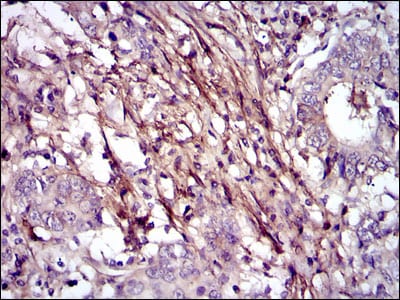

分类: 科研抗体货号: 30339别名: FN; CIG; FNZ; MSF; ED-B; FINC; GFND; LETS; GFND2应用: IHC,FCM反应种属: Human